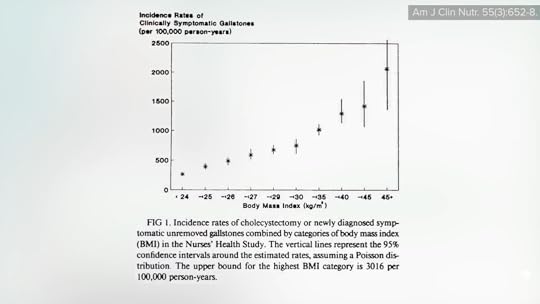

As I discuss in my video The Effects of Obesity on Gallstones, Acid Reflux, and Cardiovascular Disease, the biggest purported cause-and-effect risk factor may be obesity, increasing risk as much as sevenfold, as you can see below and at 1:32 in my video, with a doubling of risk even at the heavier side of “the normal BMI range.”